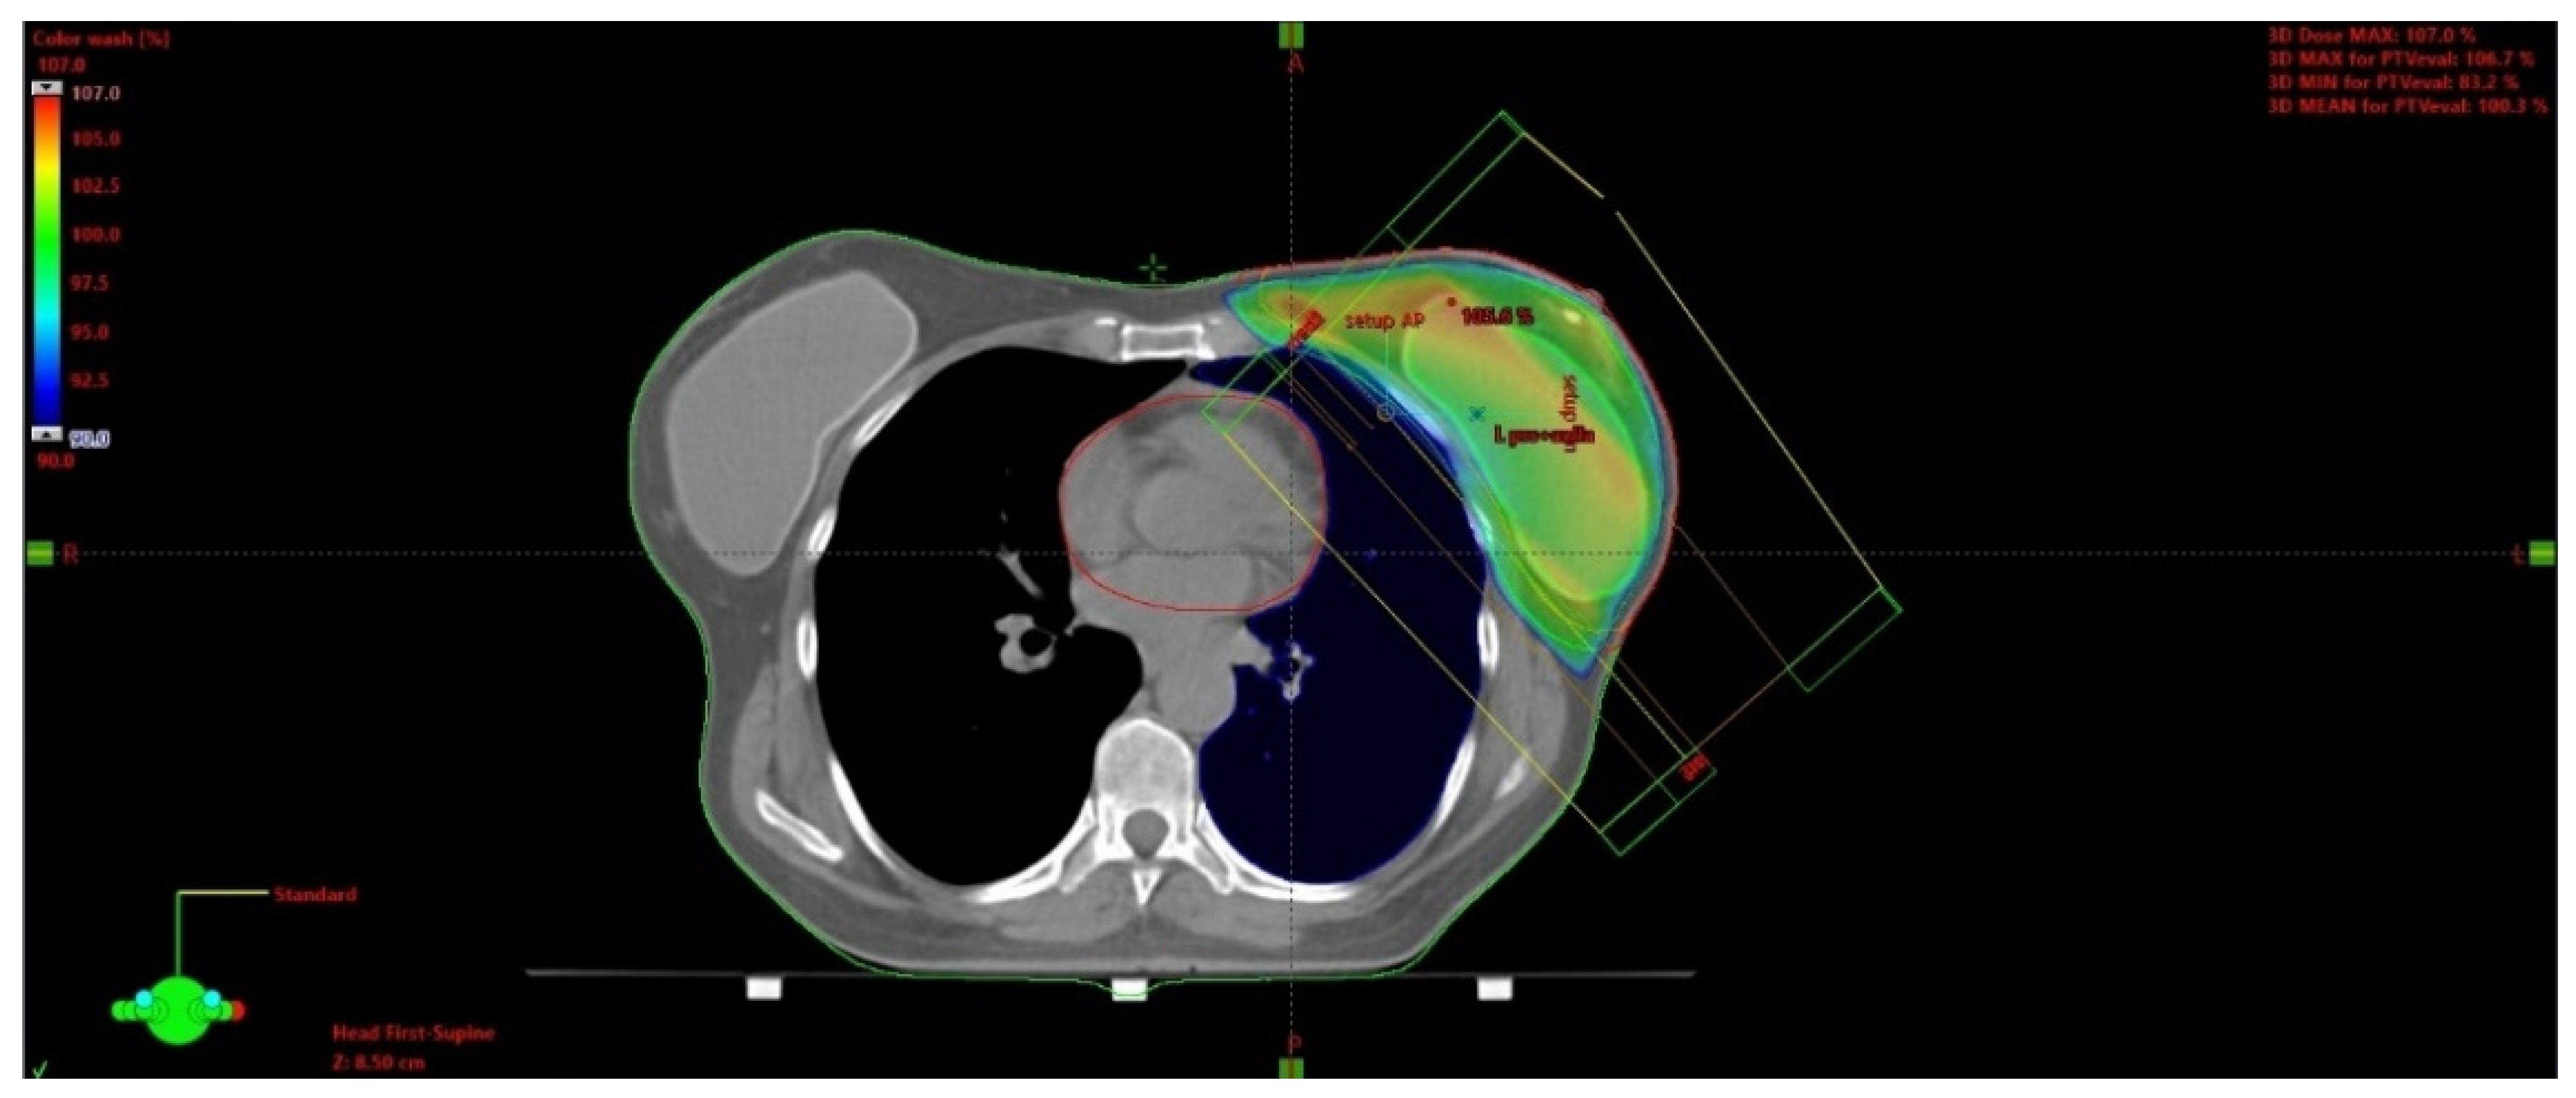

The issue of using radiotherapy in patients who have undergone immediate breast reconstruction and in whom post-mastectomy radiation therapy (PMRT) is indicated remains controversial. Available data indicate that a majority of patients undergoing immediate reconstruction have an implant placed during the surgery [58]. Figure 3 presents an isodose plan for a patient with an inserted silicone implant.

Figure 3.

Breast irradiation after radical mastectomy with silicone implant insertion. A dose greater than 90% of the prescribed dose is displayed in color. The maximum dose in this slice is 105.6 % of the prescribed dose.